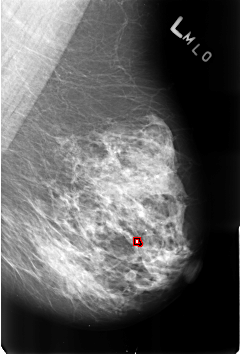

B_3174_1.RIGHT_MLO

LEFT_MLO LINES 4592 PIXELS_PER_LINE 3120 BITS_PER_PIXEL 12 RESOLUTION 50 OVERLAY

FILE: B_3174_1.LEFT_MLO.OVERLAY

TOTAL_ABNORMALITIES 1

ABNORMALITY 1

LESION_TYPE CALCIFICATION TYPE ROUND_AND_REGULAR-LUCENT_CENTER-DYSTROPHIC DISTRIBUTION DIFFUSELY_SCATTERED

ASSESSMENT 2

SUBTLETY 4

PATHOLOGY BENIGN_WITHOUT_CALLBACK

TOTAL_OUTLINES 1

BOUNDARY